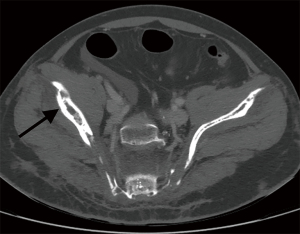

The involvement locations and incidence of bone lesions in 39 cases are detailed in Table 2. According to the morphology of bone lesions, these were divided into the following four types: (I) cystic changes (n=30; Figure 2), which showed single or multiple round-like cystic hypodense shadows in bone. The lesions had clear borders with or without sclerotic margins, and the maximum diameter was less than 5 cm. Marginal sclerotic margins (n=28), with one case showing iodized oil deposits within the lesion. (II) canal-like or honeycomb-like changes (n=34; Figure 3), which showed a tortuous, tubular distribution of hypointense shadow with clear margins and continuous at multiple levels above and below. The bone cortex was smooth or irregularly fractured in a worm-like pattern, while lesions were seen in 20 cases with iodized oil deposits. (III) Osteoporosis-like changes (n=16 cases; Figure 4), which showed a diffuse decrease in bone density and thinning of bone trabeculae. No lipiodol deposition was seen in any of the 16 cases in this group. (IV) Osteosclerosis-like changes (n=8; Figure 5), with two cases showing smooth thickening of the bone cortex, three cases showing increased density of osteophytes in the medullary cavity, three cases showing mixed presence, and five cases showing narrowing of the medullary cavity. Iodized oil deposition was not observed in any case.